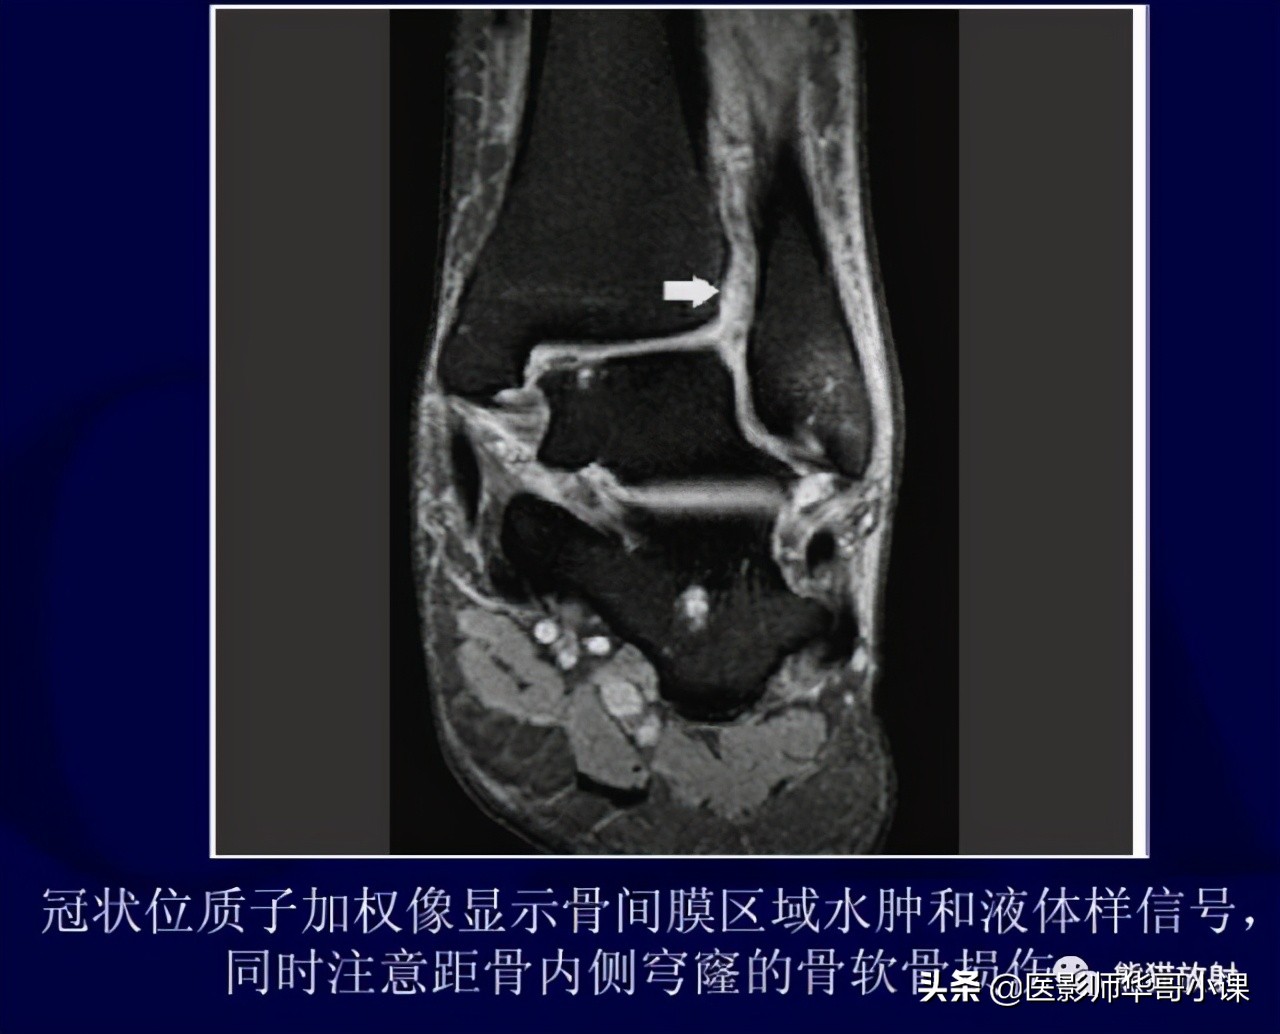

3个影像学检测指标可用于诊断踝关节下胫腓联合损伤 :胫腓骨重叠距离,胫腓间隙(tibiofibular clear space),内侧关节间隙等。

胫骨穹窿上方 1cm 处测量前后位片上胫腓骨重叠大于 6mm,或者踝穴位 X 片重叠大于 1mm 时提示正常,若前后位 X 片上重叠小于 6mm 则提示下胫腓联合损伤。

踝关节内侧间隙的宽度应和胫骨穹窿 / 距骨顶间隙相等或略小。

在负重位或非负重位 X 片上胫腓骨重叠距离减小,胫腓骨间隙或者踝穴内侧间隙增大均提示下胫腓联合损伤。

胫腓骨间隙是影像学上测量最为可靠的指标,因其很少受到下肢和射线成像的角度的影响。CT可以发现 X 片上不明显的骨折;而 MRI 对诊断下胫腓联合韧带损伤具有极高的敏感性和特异性。

胫腓联合损伤诊断测量线 :A、胫腓骨重叠,B、胫腓骨间隙,C、内踝间隙。(其中胫腓骨重叠和胫腓骨间隙的测量在距离胫骨穹窿顶1CM处。)